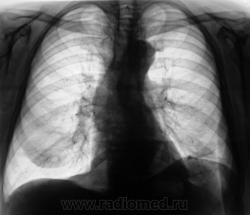

Легкие без очаговых и инфильтративных изменений, увеличены в объеме и прозрачности (эмфизема). Особенно увеличен объем язычковых сегментов левого легкого, несколько уменьшена в объеме нижняя доля. Левый купол диафрагмы расположен несколько выше нормы, особенно задние отделы, плевро-диафрагмальная спайка, увеличено расстояние до газового пузыря желудка. Предварительное заключение: подозрение на нарушение бронхиальной проходимости в левом легком, базальный гидроторакс слева. Дообследование: линейная томография (боковая проекция обязательна, может быть очень информативной), латерография для исключения/подтверждения свободной жидкости в левой плевральной полости.

Легкие без видимых очаговых и инфильтративных измнений. По прямой рентгенограмме левая половина диафрагмы расположена выше обычного. Прозрачность левого легочного поля выше правого. При изучении левой боковой рентгенограммы нижняя доля левого легкого резко уменьшена в объеме в пределах анатомических границ. Затенение базальных отделов левого легочного поля на фоне которого не дифференцируется левая половина диафрагмы. Викарная эмфизема верхней доли левого легкого.

Заключение(вывод): больше данных за ателектаз нижней доли левого легкого (гиповентиляция). Необходимо дополнительное исследование проходимости бронхиального дерева левого легкого. Бронхоскопия, ТМГ, КТ.

Слева в нижних отделах пневмофиброз, приподнятость диафрагмы, асимметрия грудных мышц или молочных желез - возможно было лучевое лечение опухоли левой молочной железы??? Если нет - Узи живота, бронхоскопия.

СЛЕВА ЗА 6 РЕБРОМ  ЛАТЕРАЛЬНО

ВРОДЕ БЫ ИМЕЕТСЯ  НЕБ. УЧАСТОК  УПЛОТНЕНИЯ ( НА  БОКОВОМ НЕ НАХОЖУ, ГДЕ).

СЛЕВА НАД  ДИАФРАГМОЙ  ЕДИНИЧНЫЕ  ЛИНЕЙНЫЕ  ШВАРТЫ,

ЗАДНИЙ СИНУС  ОБЛИТЕРИРОВАН, ЛЕВ.  КУПОЛ ДИАФРАГМЫ ПРИПОДНЯТ.

ФИКСИРОВАН  ПЛЕВРО-ДИАФР. СПАЙКАМИ. ХОРОШО БЫ ЗНАТЬ АНАМНЕЗ - ЧТО И КОГДА  БЫЛО СЛЕВА?

Ателектаз нижней доли левого л1гкого.

Что-то на ателектаз не похоже. Какие-то плевральные штучки.